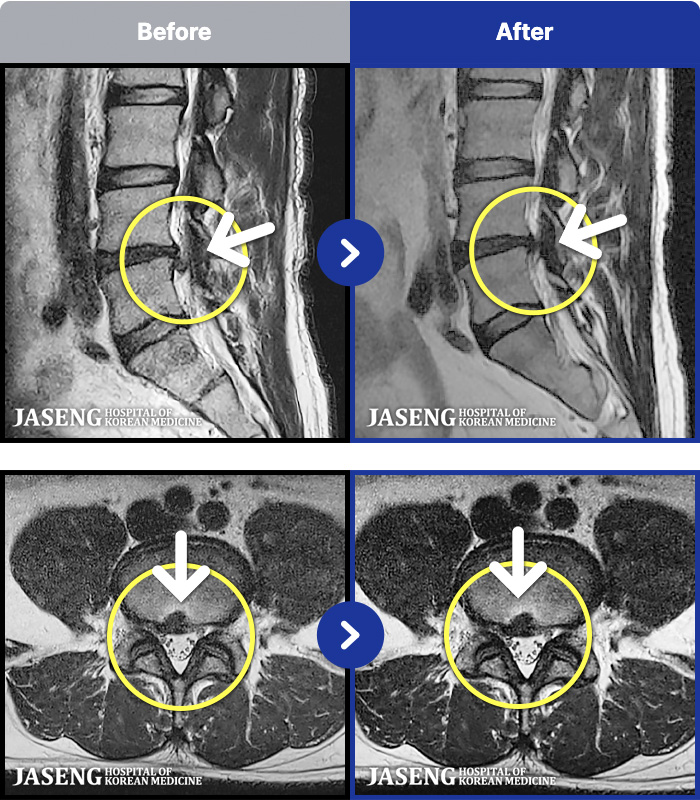

- MRI ġ

MRI ġ

1,237 MRI ũ ʸ Ȯϼ.